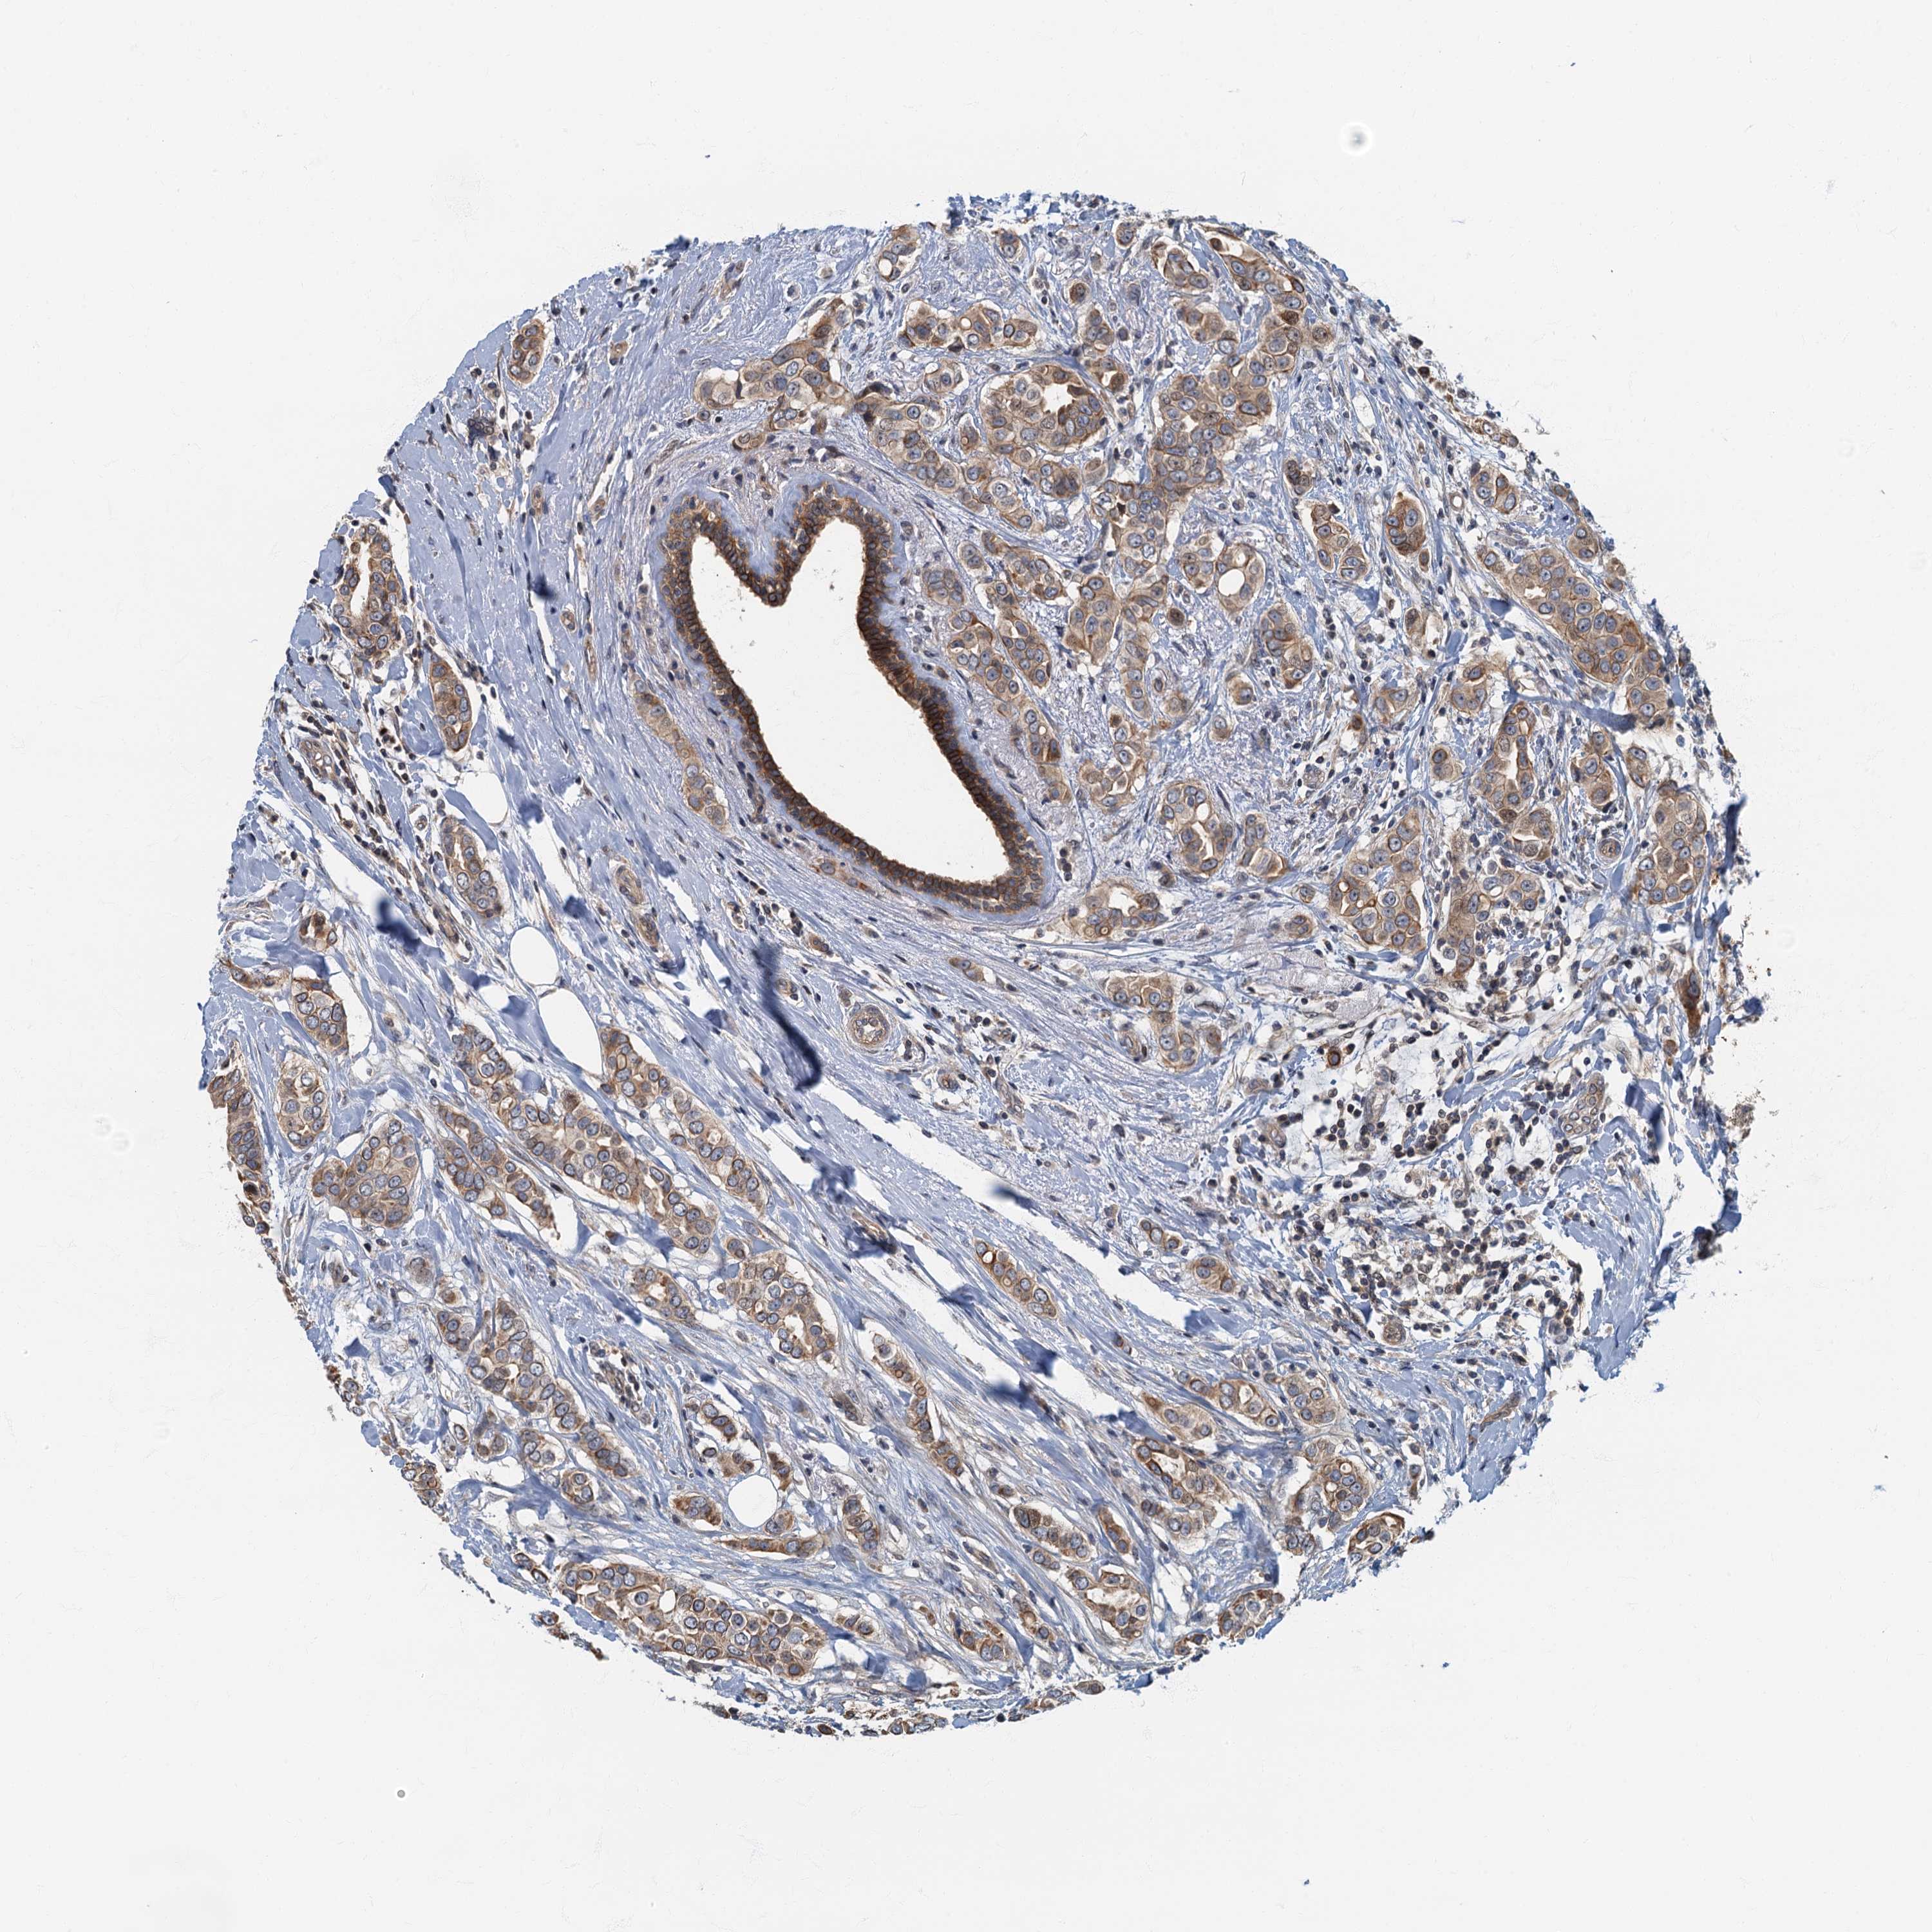

CANCER BREAST CANCER Show tissue menu

BRCA TCGA BRCA VALIDATION PROTEIN EXPRESSION